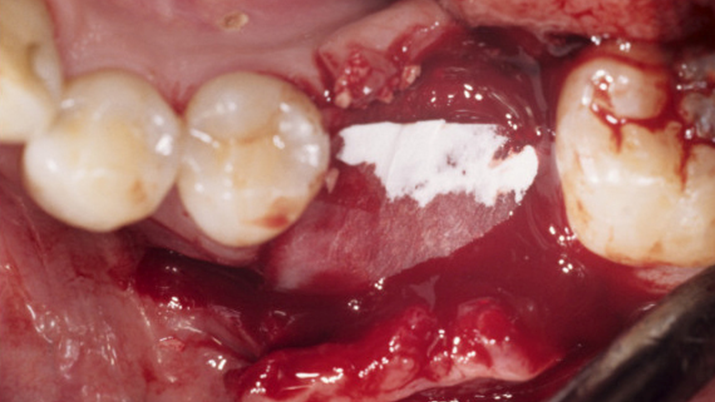

Clinical case: Single molar implant with bone augmentation

- Courtesy of Dr. Jung Sam Lee, Korea -

AnyOne, bone augmentation, osteotomy socket, peri-implant tissue, autogenous bone, GBR, single replacement, Auto-Max, Dr. Jung Sam Lee

AnyOne implant system, Auto-Max